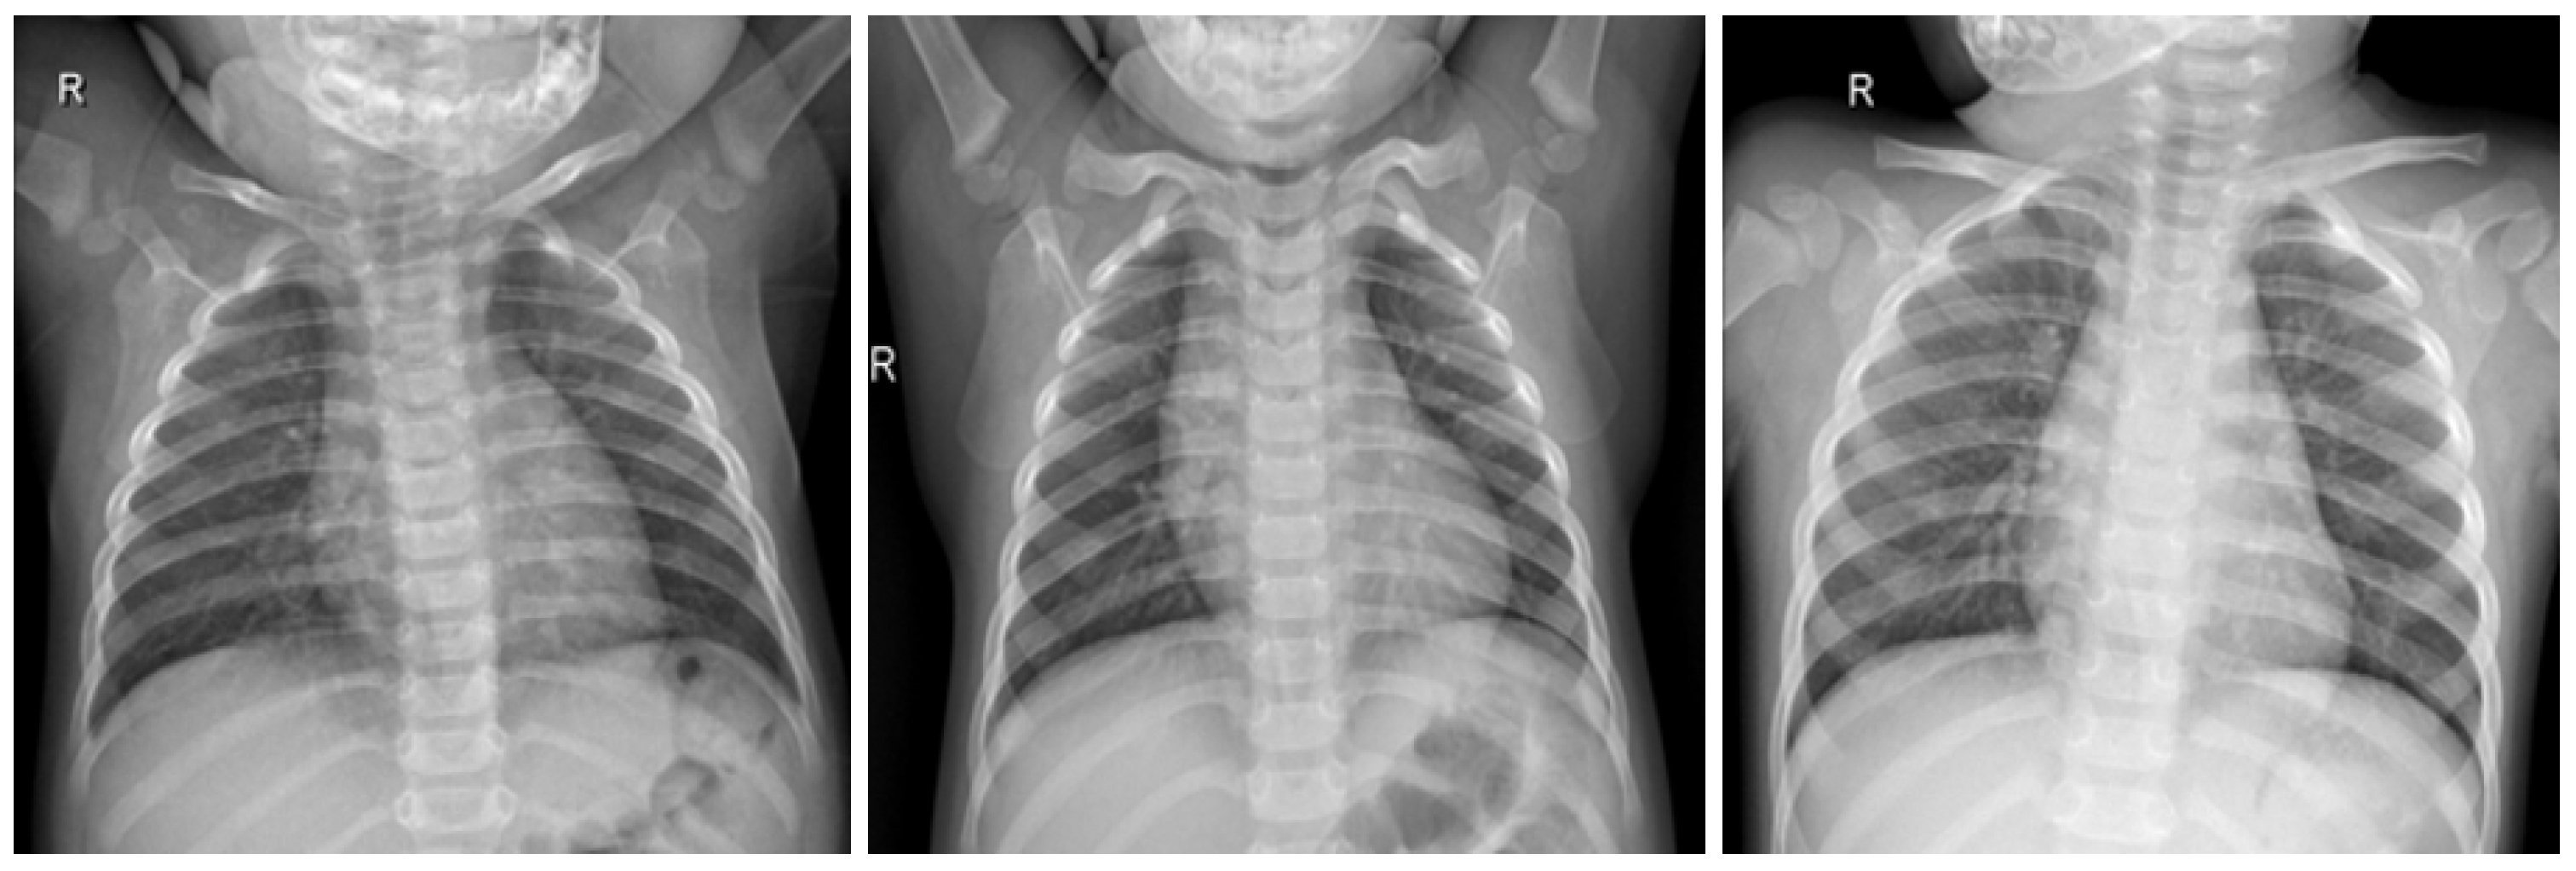

In this work, a COVID-19 radiography dataset collected in previous works related to a COVID-19 detection model [24,25] was used. The dataset contains X-ray lung images with four different classifications, which are COVID, Lung_OPACITY, Normal, and Viral Pneumonia. In this work, we utilized two classifications, which are COVID and Normal, focusing only on the COVID-19 detection machine learning process.

Figure 4.

COVID-19 negative X-ray image dataset samples.